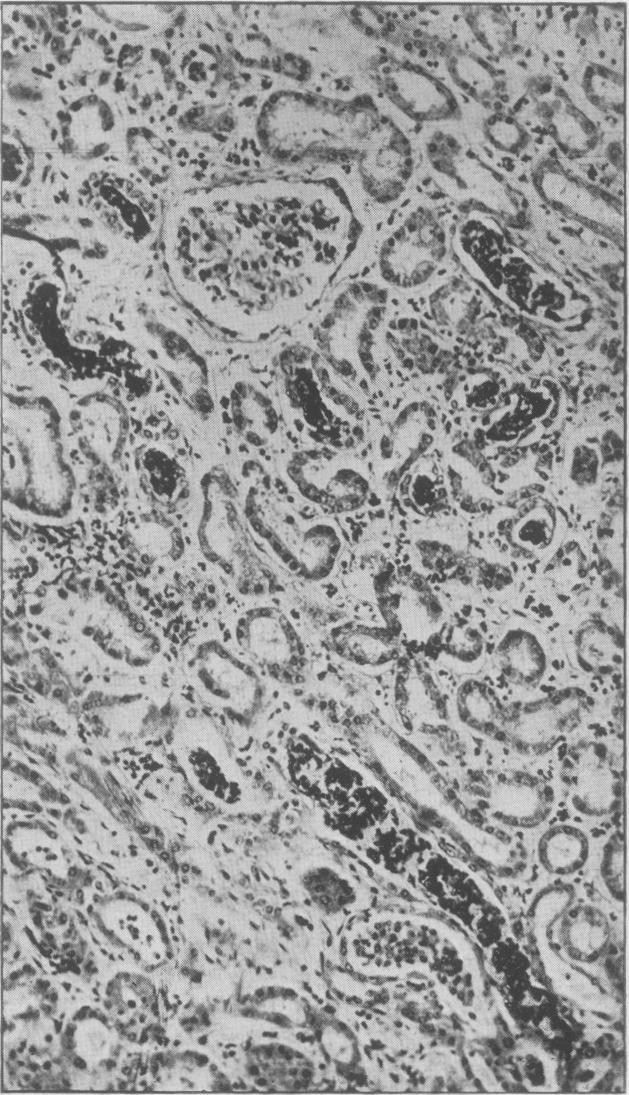

Discussion on the pathological features of cortical necrosis of the kidney and allied conditions associated with pregnancy.

Proc R Soc Med. 1949 Jun;42(6):375-87. doi: 10.1177/003591574904200601.